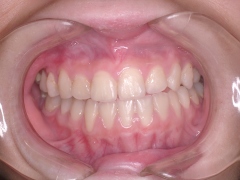

下顎前突(埋伏歯)

治療前 正面

受け口です

治療後 正面

正常になっています